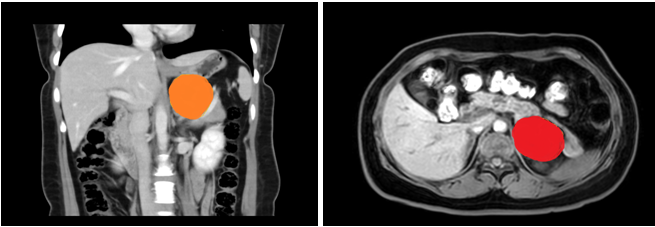

患者,女性,35岁,在21点技巧中心 上腹部CT增强示:左侧腹膜后囊性病变,支气管囊肿不除外;入院后上腹部MRI平扫+DWI+增强扫描+MRCP示:左侧肾上腺上方囊性病变,考虑来源腹膜后间隙,1)支气管源性囊肿2)淋巴管囊肿可能,建议复查。

在张煜副主任带领下,经过肝胆外科全科细致讨论,认为占位较大,位置靠后,微创难度大,需完善相关检查,精细术前准备。经过医护一体化管理,打消了患者的术前顾虑,在全麻下行腹腔镜下腹膜后囊性占位手术+广泛腹腔粘连松解术,手术顺利,术后病理结果为良性,患者术后一周内顺利出院。患者表示,术后经过了解,得知此例手术难度较大,目前恢复良好,特意送来锦旗表达感谢。